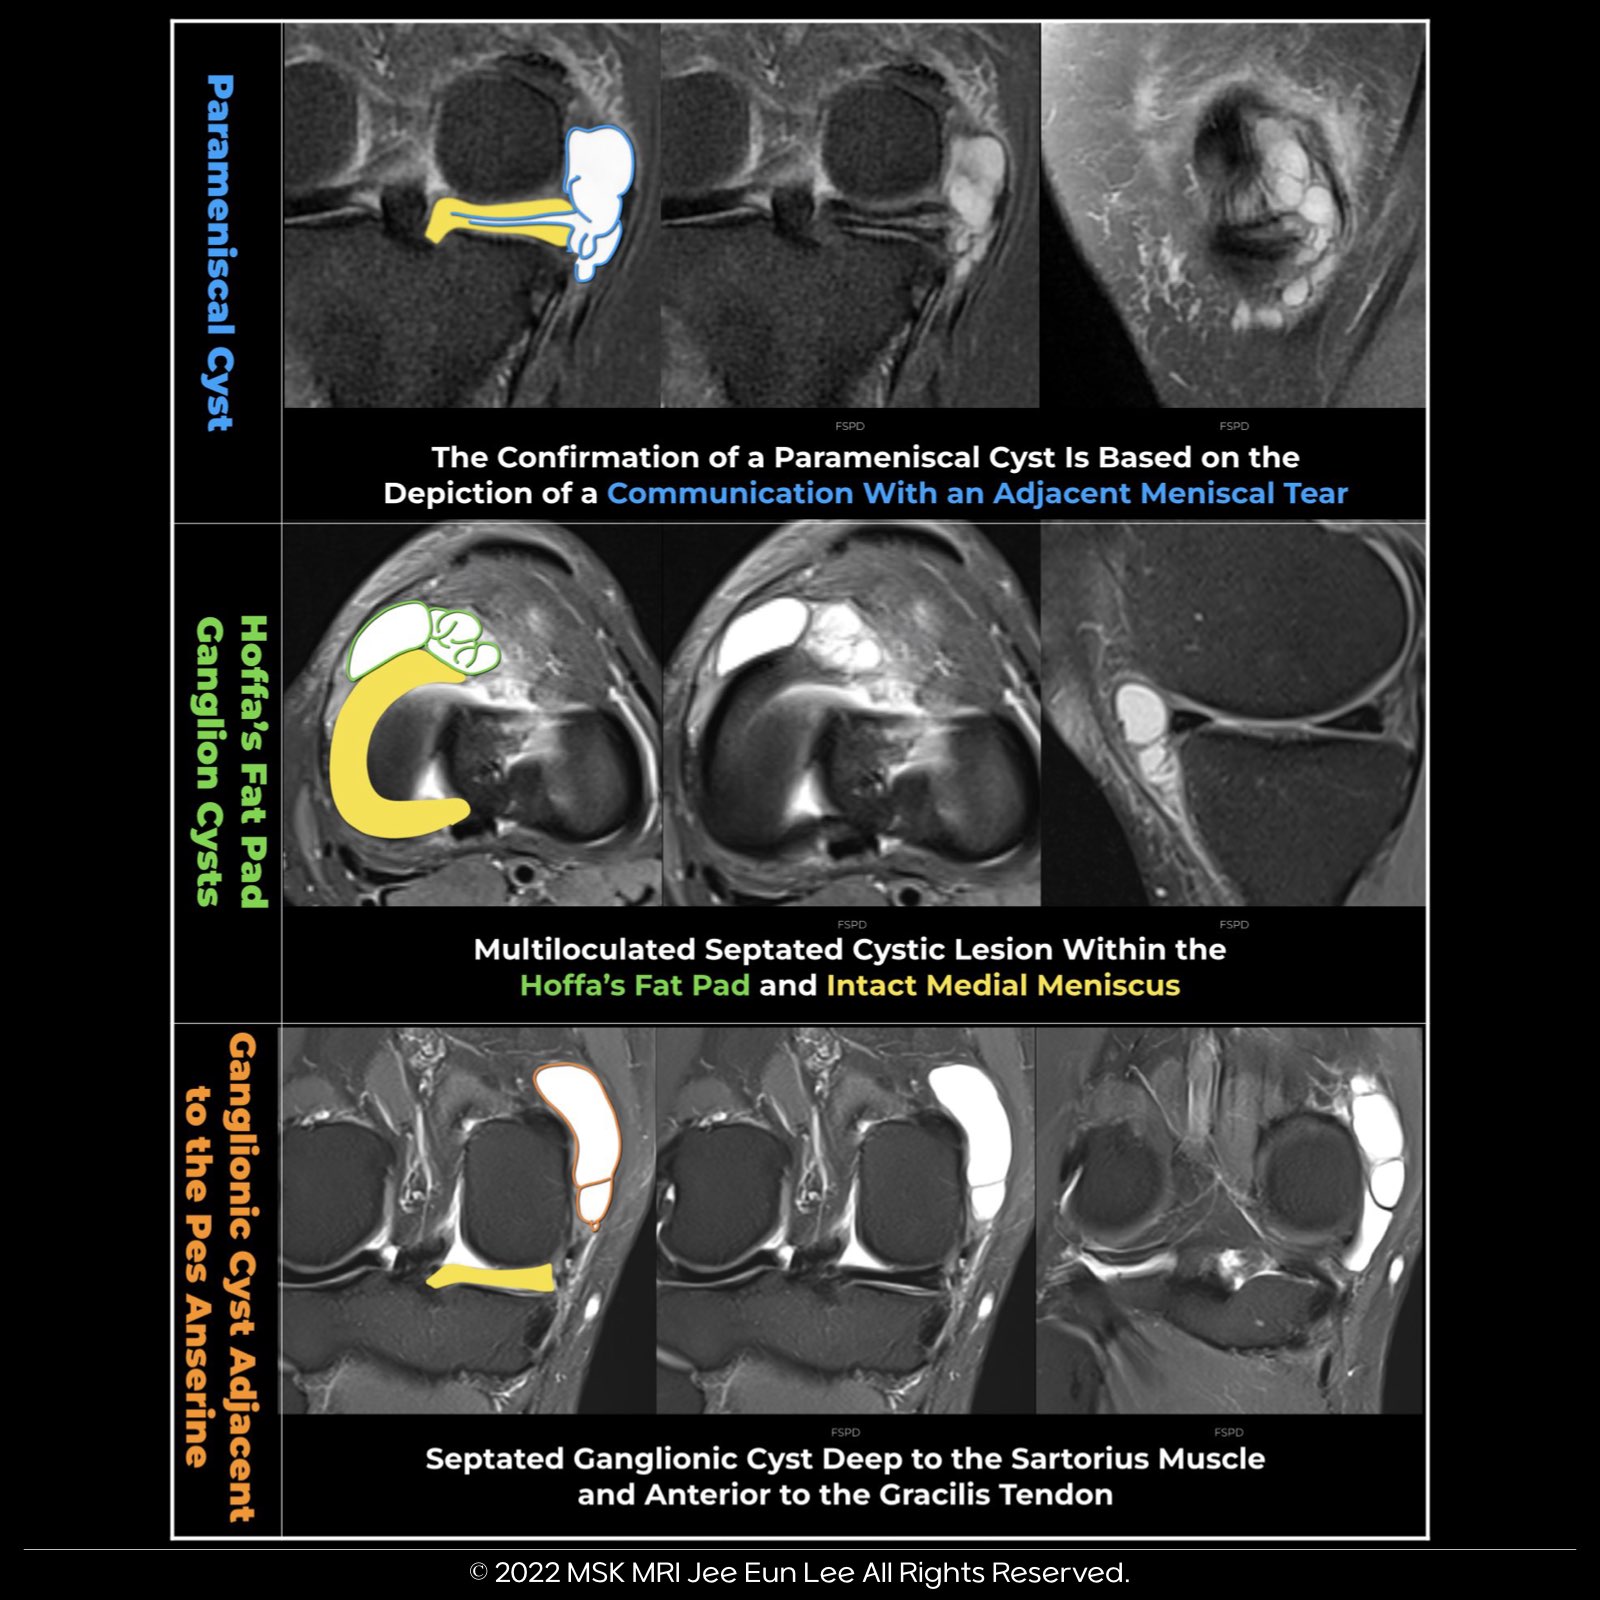

1️⃣ Parameniscal Cyst

- Can appear similar to a ganglion but is usually smaller.

- Typically associated with an underlying meniscal tear.

- Diagnosis confirmed by showing a connection with an adjacent meniscal tear on MRI, regardless of the pulse sequence used.

2️⃣ Infrapatellar Ganglion

- Well-marginated masses located at the anterior knee.

- Filled with gelatinous material and lack a synovial lining.

- Most commonly found in the Hoffa fat pad, adjacent to the anterior horn of the lateral meniscus.

✅ MRI Appearance

- Appears as a well-defined, homogeneous, non-enhancing fluid-filled collection.

- Rupture or leakage can cause ill-defined adjacent edema.